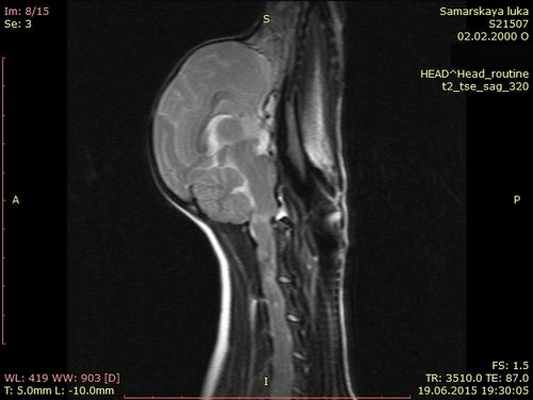

На мрт исследовании нашего пациента – здесь представлена сагитальная Т2 взвешенная последовательность, определяется смещение аксиального позвонка в дорсальном направлении по отношению к атланту, дислокация дорсальной дужки атланта к задней черепной ямке с тяжелой компрессией как мозжечка, так и спинного мозга.